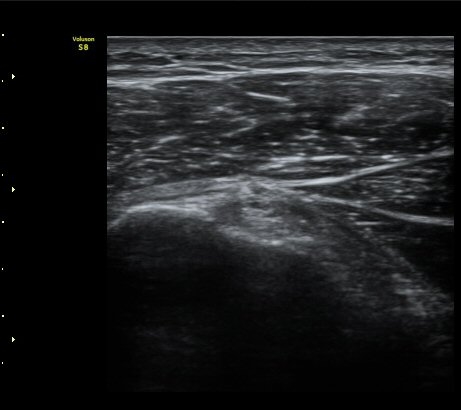

±Ø»ó°Ç Á¾´Ü¸é°Ë»ç¿¡¼­ ±Ø»ó°Ç ÆÄ¿­Àº º¸ÀÌÁö ¾ÊÀ¸³ª »ó¿Ï°ñ ´ë°áÀý°ú °ñµÎ ÀÌÇàºÎÀ§¿¡¼­

ÇÇÁú°ñ ¿¬°á ¼Ò½Ç°ú ¹Ì¼¼ÇÑ °ñÆíÀÌ °üÂûµÊ(»çÁø 3, 4, 5).